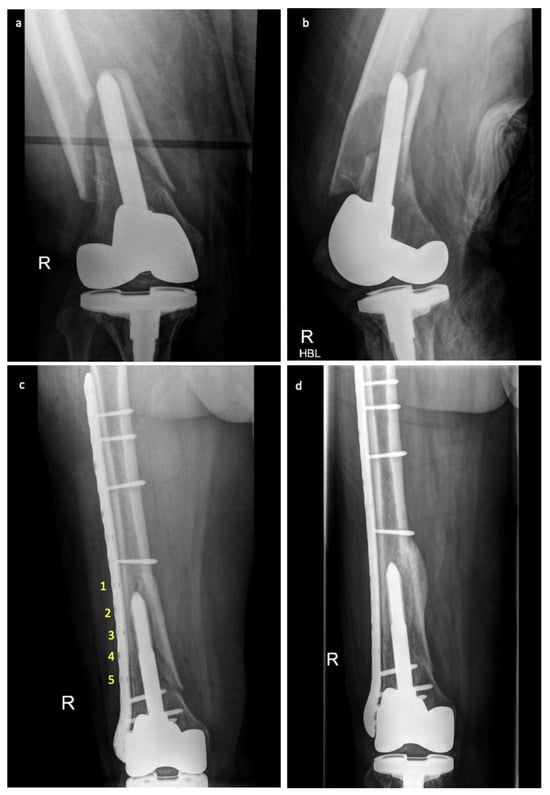

Figure 2. Plain film radiographs pre- and post-fracture fixation with far cortical locking screws for a periprosthetic distal femur fracture. (a) Anterior-posterior and (b) lateral views of the initial fracture. (c) Anterior-posterior view (working length labelled 1–5) day one and (d) six months post-fracture fixation with far cortical locking screws and plate constructs showing evidence of callus formation.